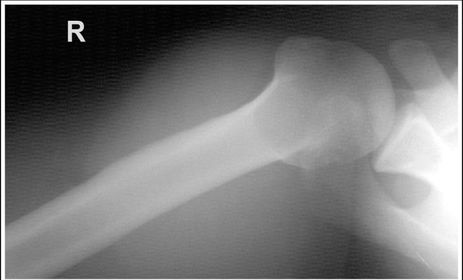

| Lateral Elbow | The elbow is elevated above the level of the shoulder radial head anterior to coronoid - should be superimposed capitulum too proximal to trochlea radial tuberosity seen - hand is pronated |

| Lateral Elbow | Elbow is depressed below the level of the shoulder radial head superimposed by coronoid capitulum too distal to medial trochlea |

| Lateral Elbow | the distal wrist is elevated hand is pronated because you can see the radial tuberosity - should not see that |

| Lateral Elbow Evaluation Criteria | ANATOMY: distal humerus, proximal forearm, entire elbow joint CRITERIA: humeral epicondyles are superimposed radial tuberosity is invisible (if visible the hand is pronated) half of the radial head superimposed by coronoid process Elbow is flexed 90 degrees to see/not see fad pads 3 concentric arcs visible POSITIONING: CR perpendicular @ lateral epicondyle |